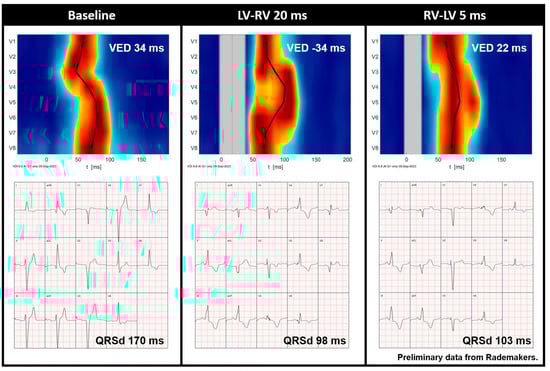

Figure 6.

Preliminary data from Rademakers et al. demonstrating the UHF-ECG activation map and averaged ECG of a CRT recipient before implantation and during various VV interval settings. Red indicates the time (horizontal axis) and location (vertical axis) when most myocardial cells are activated simultaneously. It is noteworthy that QRS duration is relatively short during an LV-RV of 20 ms, whereas the UHF-ECG reveals dyssynchronous activation. In contrast, an RV-LV of 5 ms results in more synchronous activation (ventricular electrical delay, 22 ms). Abbreviations: QRSd = QRS duration, VED = ventricular electrical delay.